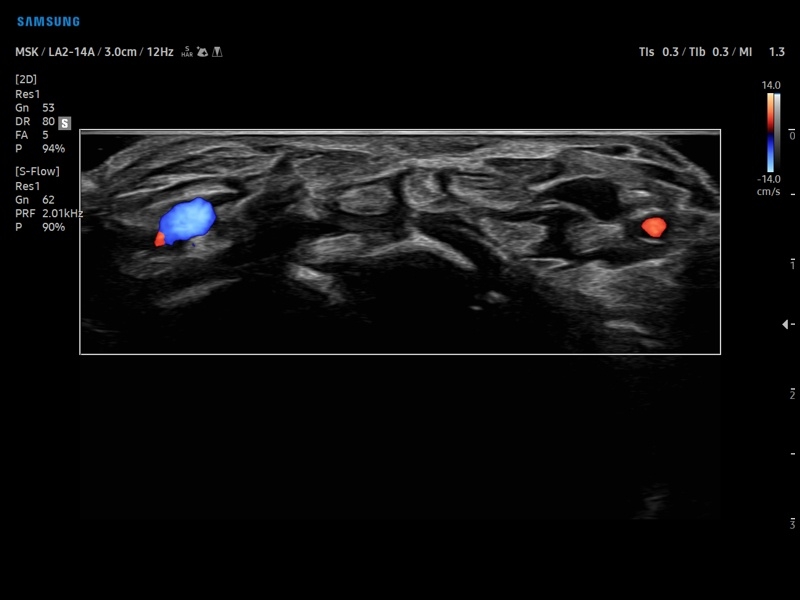

• Модуль NerveTrack – автоматическое определение срединного нерва в поперечном сечении с использованием искуственного интеллекта.

• Модуль S-Shearwave imaging – программа цветовой сдвиговой эластографии позволяющая автоматически определять индекс жесткости различных участков исследуемого объекта в кПа или м/с, получая при это еще и индекс достоверности данных RMI.